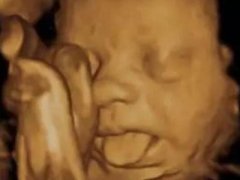

四维彩超那么贵不懂这些就白做了

四维彩超那么贵不懂这些就白做了...